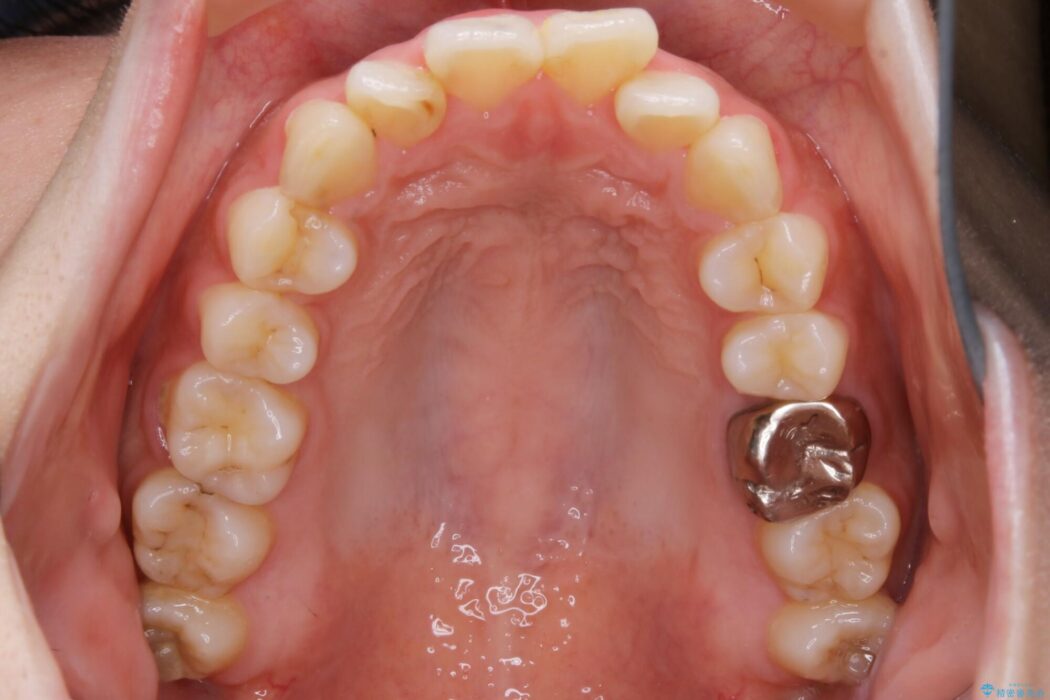

口ゴボに加えて歯列のガタガタを改善したいと来院されました。

患者様のご希望によりインビザライン装置での治療を行いました。

インビザラインは歯を後ろへ動かす動き、非抜歯での矯正治療が得意なため、ワイヤー装置では難しいケースでも対応できる場合があります。

口元が後方に下がったことにより横から見たEラインが改善し、口元の印象が変わったと患者様にとても喜んでいただけました。

矯正治療において歯並びを整えるためにはスペースが必要になります。

抜歯・歯列幅の拡大・IPR(歯と歯の間を少し削って小さくする)・歯の後方移動などでそのスペースを確保します。

程度にもよりますが口元を下げる治療というと抜歯治療を思い浮かべると思いますが、インビザラインは抜歯をせずとも他の3種類の方法を効率よく活用し治療ができます。